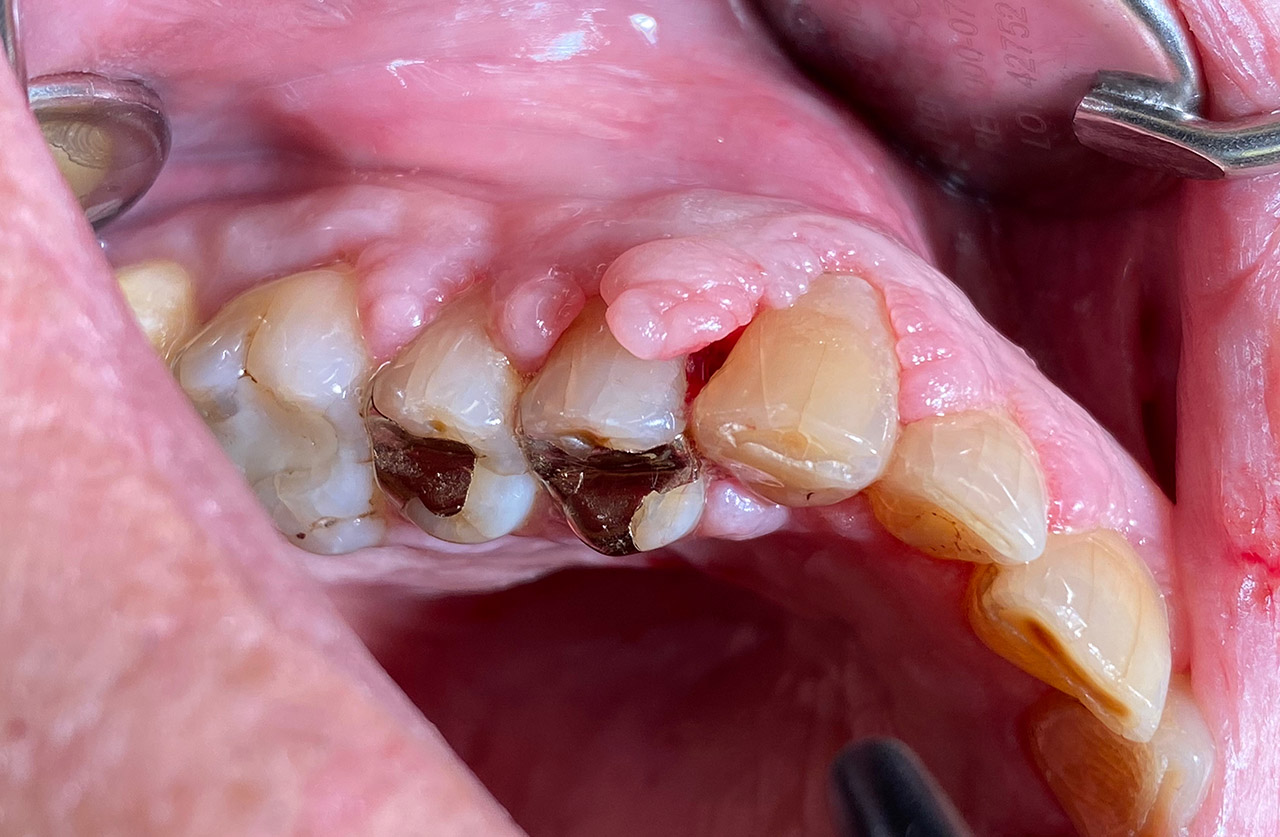

Parodontologie/Gingivahyperplasie:

Diagnose: Gingivahyperplasie durch Medikamente (Blutdrucksenker), unzureichende/nicht mehr mögliche Mundhygiene und überstehende Füllungen.

Therapie: Gingivektomie und anfinieren der Füllungen. Letztes Foto 1 Woche postOP.